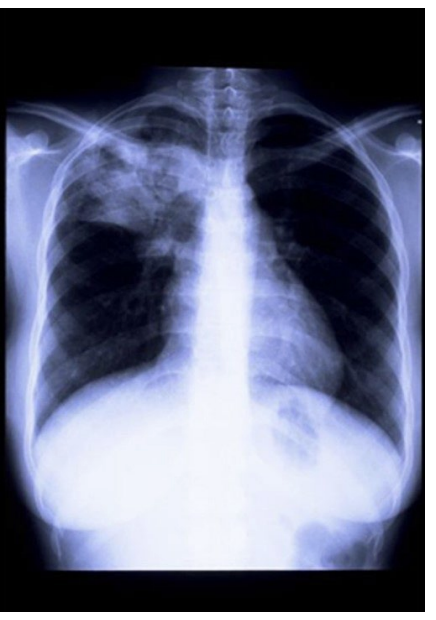

A 17-year-old adolescent girl presents with dyspnea. It is persistent and chronic for 3 months. She also elicits productive, cough, fever, and night sweats of a persistent, chronic nature; chronic bright red hemoptysis; pleuritic chest pain; and loss of appetite. On physical examination, chest crackles are appreciated in the right upper lobe, accentuated after a short cough. Chest radiography is performed as shown. Of the following, what is the most likely location for an anterior Chapman point in this patient?

On the right, 3rd intercostal space, medially